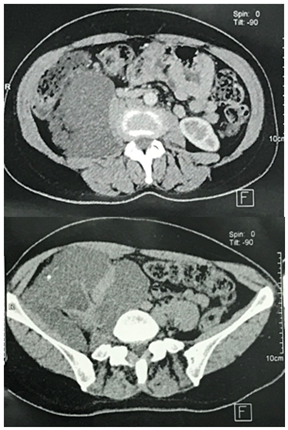

We present here the case of a 50-year-old woman who consulted for a mild right low back pain with palpable abdominal mass since several months. The clinical examination revealed a painless tumefaction of the right iliac fossa (Figure 1). A CT-scan performed showed a large right retroperitoneal cystic polylobed mass, well limited, measuring 15 cm x 10 cm x 9 cm, pushing forward the digestive loops and pushing up the right kidney, containing calcifications, without enhancement after contrast injection, and without evidence of adjacent structures infiltration, evoking a retroperitoneal cystic lymphangioma (Figure 2) and (Figure 3). The patient underwent an exploratory laparotomy, which showed a large whitish retroperitoneal cyst, extending from the right iliac fossa to the right hypochondrium (Figure 4). Given the appendix was not individualized, we suspected then, during surgery, an appendiceal mucocele. During dissection, we assisted to a tumoral rupture, and approximately 500 milliliters of a thick, gelatinous mucoid substance was sucked. The peritoneal cavity was already protected by surgical drape. We went an en-bloc and complete resection of the tumor (Figure 5). The post-operative course were normal. The histological study concluded to a mucinous cystadenoma (Figure 6). After a one-year follow-up, control CT-scans showed no signs of recurrence.

Figures 2 & 3 CT-scan showing the mass pushing forward the digestive loop, without infiltration and contrast enhancement.